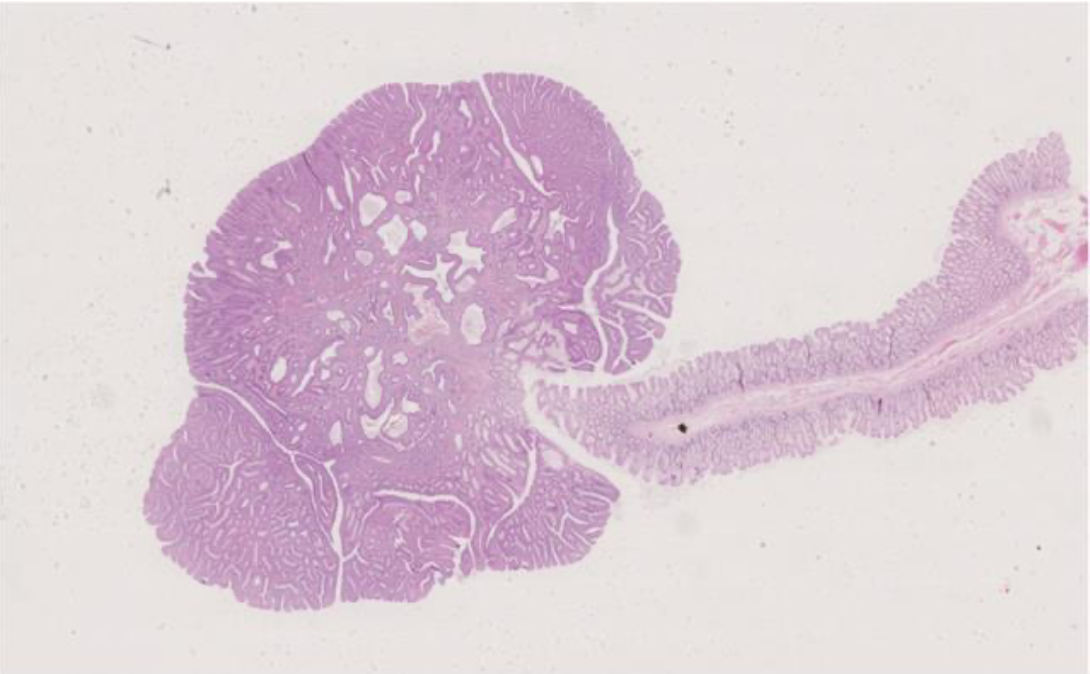

Hvilken neoplasi foreligger?

b. Colonadenom

*b. Colonadenom